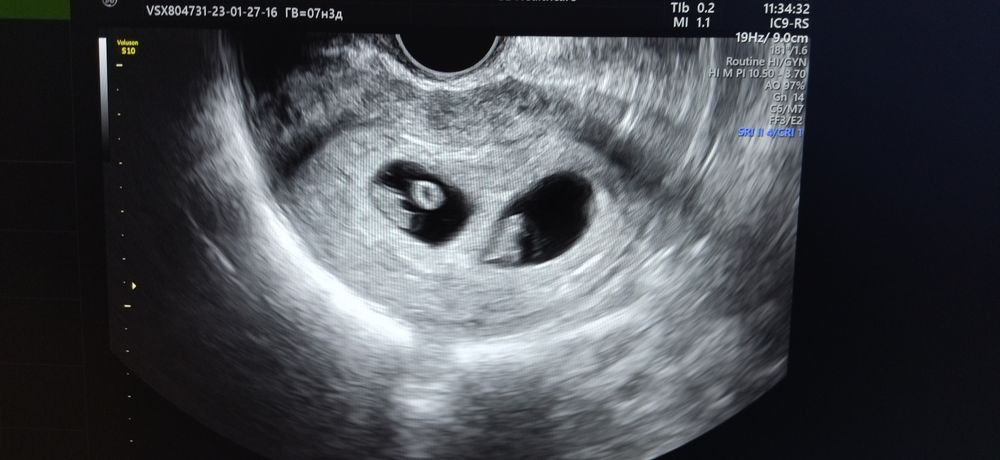

Ди-ди, 7 недель и 3 дня.